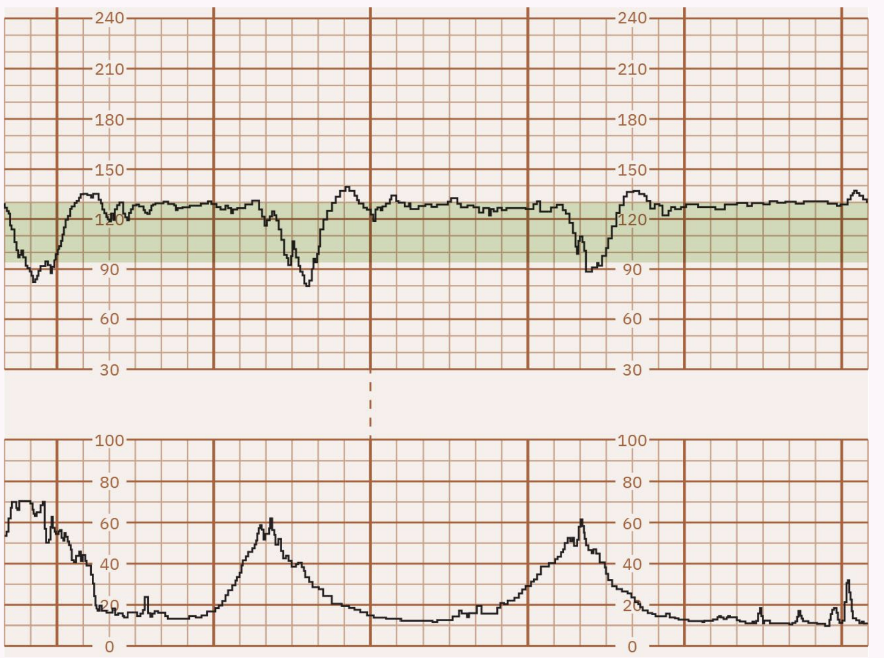

Moderate: Range bpm; indicative of fetal well-being and adequate oxygenation.

this is what we want!! very happy baby!

Category I (Normal): Baseline bpm, moderate variability, no late or variable decelerations, accelerations present/absent, early decelerations present/absent